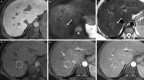

![CT images show examples of observations that meet criteria for Liver

Imaging Reporting and Data System (LI-RADS) category LR-M (probably or

definitely malignant, not hepatocellular carcinoma [HCC] specific). Axial

contrast-enhanced CT in (A) arterial phase and (B) portal venous phase in a

56-year-old woman with nonalcoholic steatohepatitis-induced cirrhosis

demonstrates a 36-mm observation (arrow, B) with rim arterial phase

hyperenhancement (arrow, A). Pathology revealed intrahepatic

cholangiocarcinoma. Axial contrast-enhanced CT in (C) arterial phase and (D)

portal venous phase in a 63-year-old man with hepatitis C virus cirrhosis

demonstrates a 90-mm observation (arrow, D) with rim arterial phase

hyperenhancement (arrow, C). Pathology revealed poorly differentiated HCC

with p53 mutation.](https://cdn.ncbi.nlm.nih.gov/pmc/blobs/b9f2/10068888/acbd0f3a2a67/radiol.222801.fig7.gif)